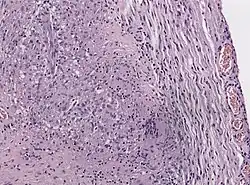

Neuro-ophthalmologic examination showing ophthalmoplegia in a patient with Tolosa–Hunt syndrome, prior to treatment. The central image represents forward gaze, and each image around it represents gaze in that direction (for example, in the upper left image, the patient looks up and right; the left eye cannot accomplish this movement). The examination shows ptosis of the left eyelid, exotropia (outward deviation) of the primary gaze of the left eye, and paresis (weakness) of the left third, fourth and sixth cranial nerves. | |